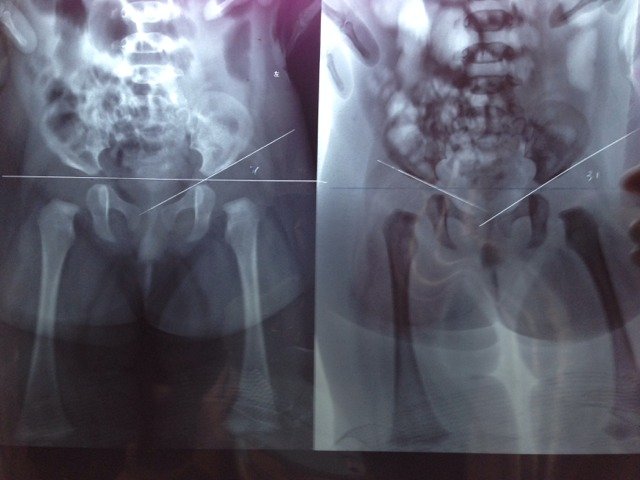

医生,能不能帮帮忙看看四个月宝宝照的x光片,看看宝宝的髋关节发育是不是有问题,需要怎么办呢?谢谢了

您好,这个问题还是比较明显的,有一侧(您提供的图片的最左边)髋关节的髋臼基本上是没有发育的,所以这个肯定是要进行手术治疗的